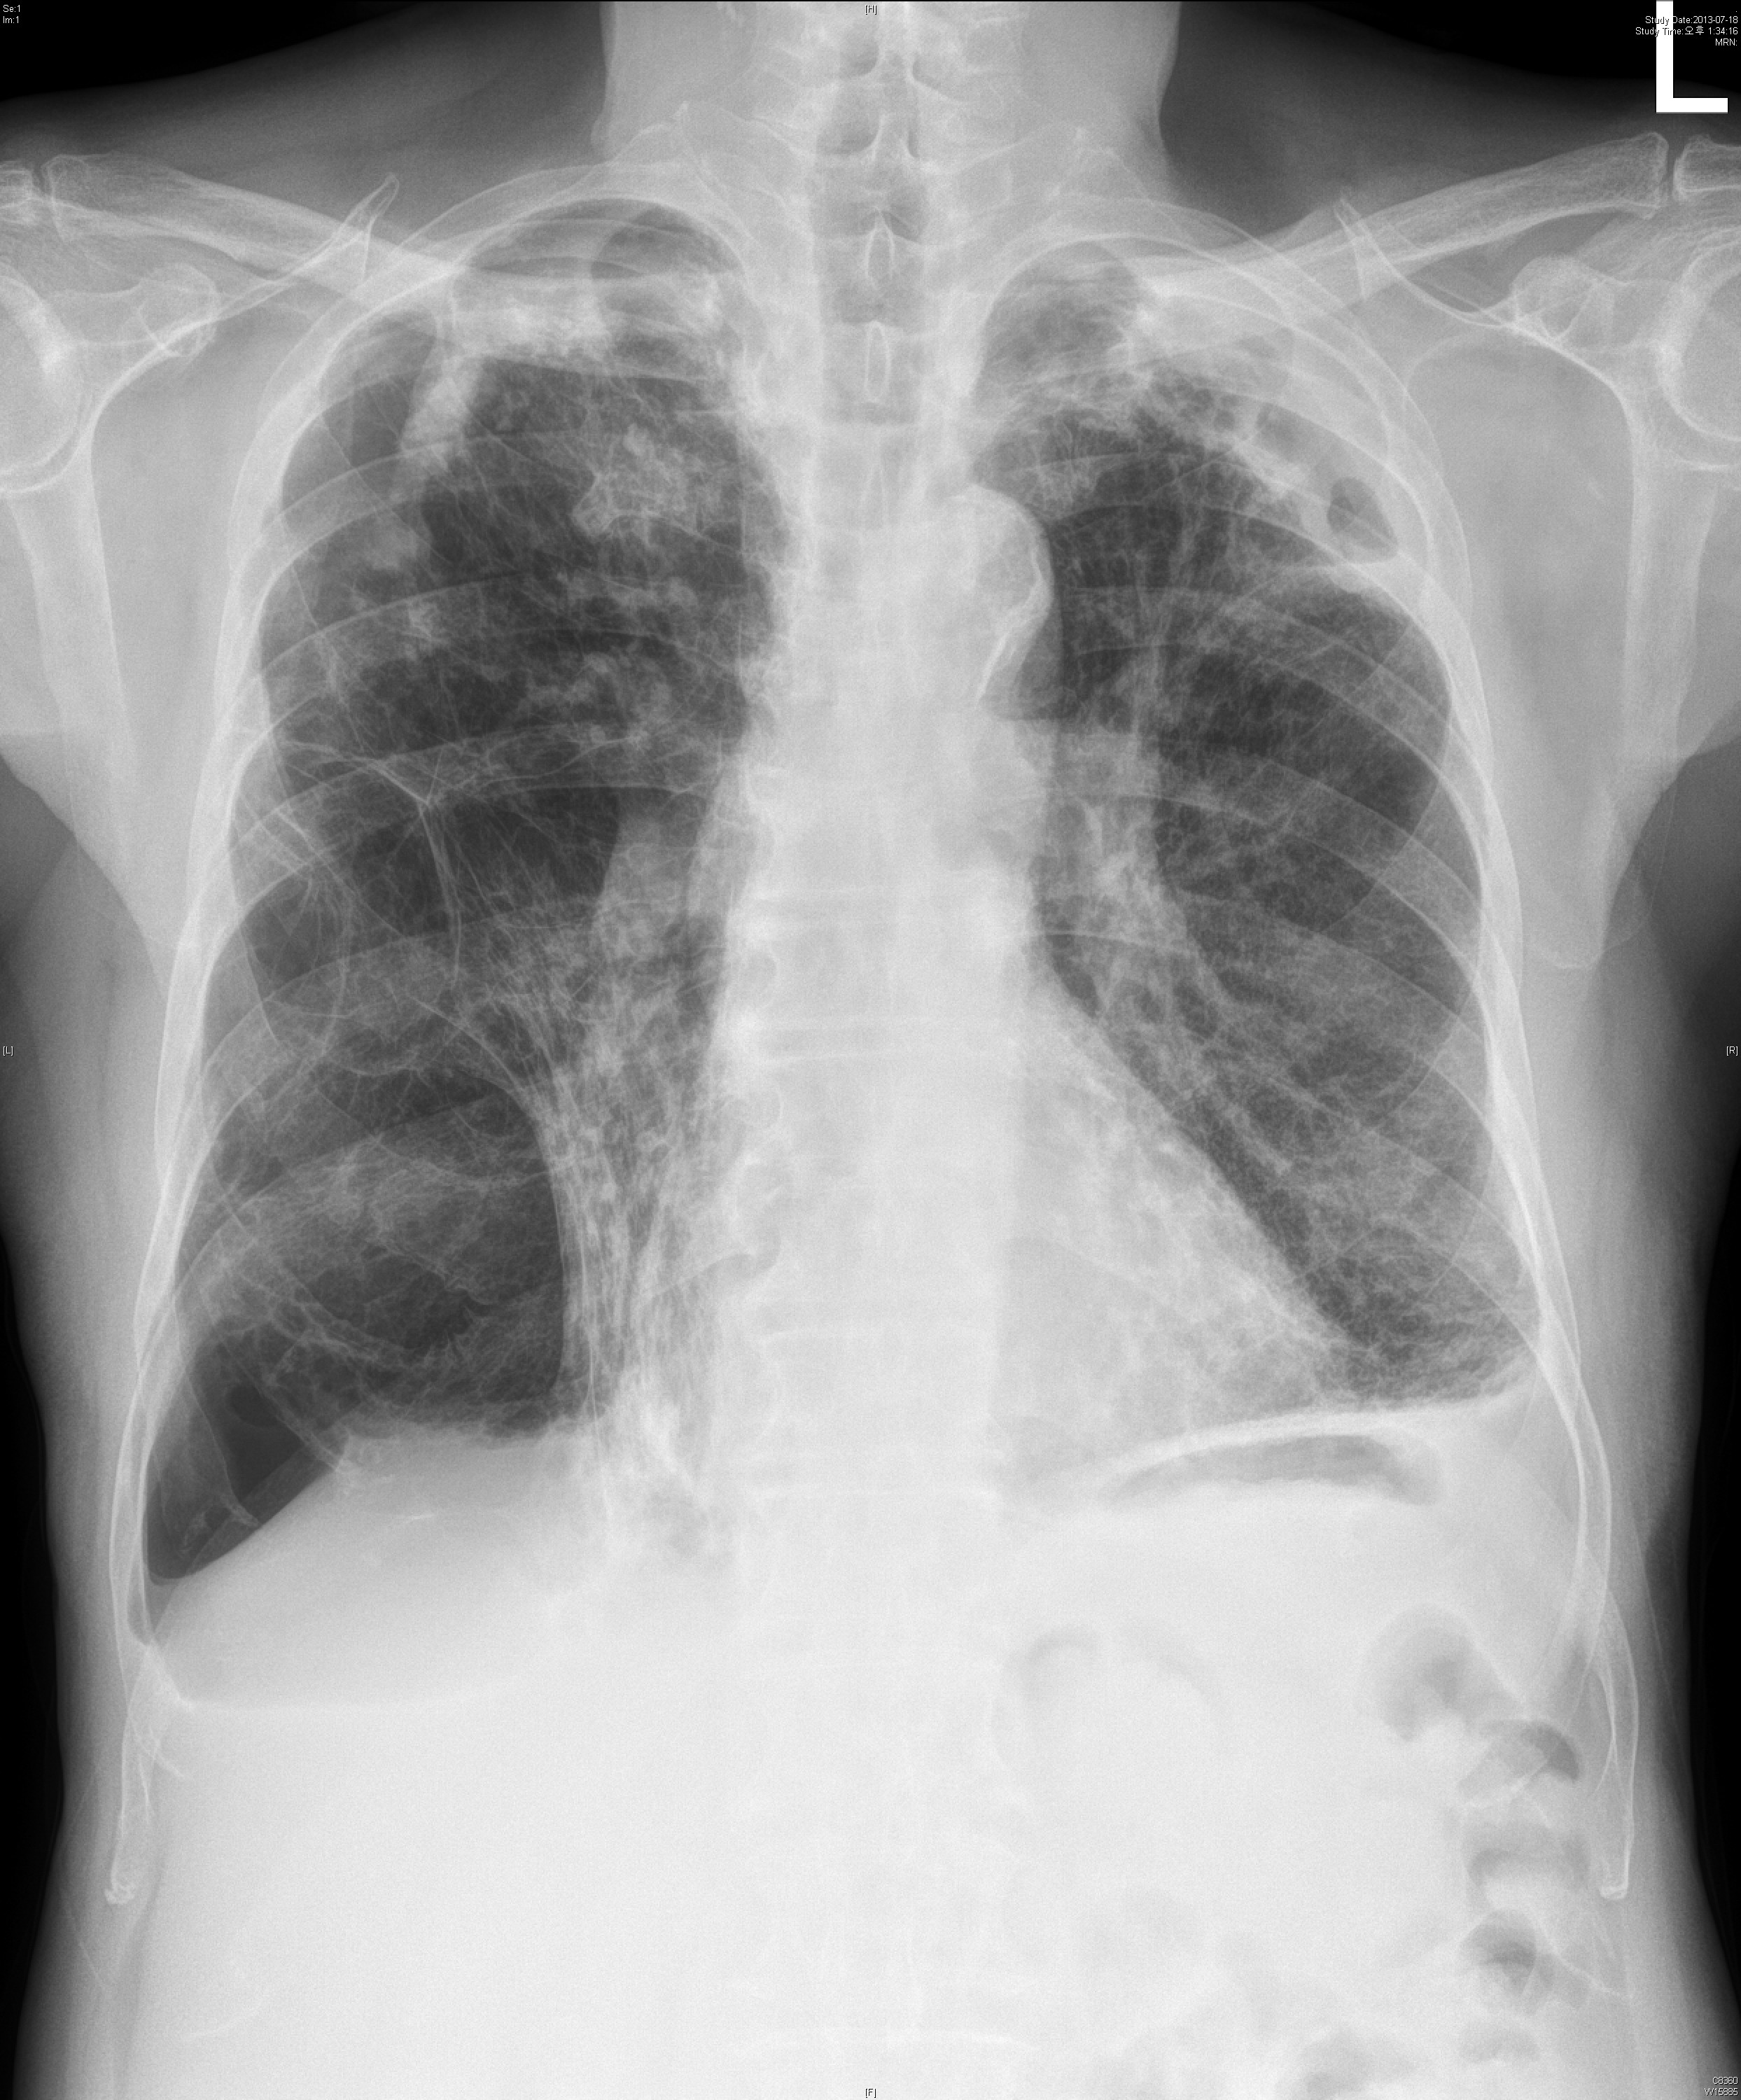

74¼¼ ³²È¯À¸·Î COPD grade A, CAOD, prostate cancer ·Î f/u ÁßÀ̾ú½À´Ï´Ù.

¾à ¿­Èê ÀüºÎÅÍÀÇ °¡½¿ ÅëÁõ ¹× È­³ó¼º °´´ãÀ» ÁÖ¼Ò·Î ³»¿øÇÏ¿´½À´Ï´Ù.

ÁÂÃøÇϺο¡¼­ crackles ûÁøµÇ¾ú½À´Ï´Ù.

6°³¿ù ÀüÈÄÀÇ »çÁøÀÔ´Ï´Ù.